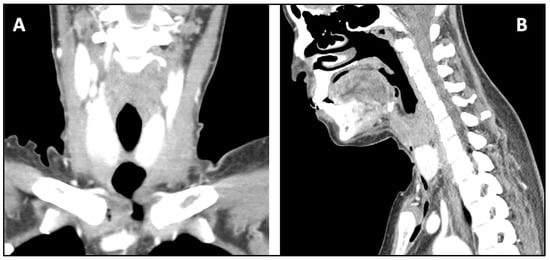

2. Case Report